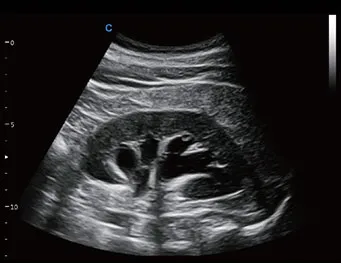

Modo M de dirección libre

● Obtener datos precisos de análisis de la función cardíaca.

● Obtenga parámetros de medición cardíacos precisos de cualquier sección y cualquier ángulo.

● Excelente y conveniente para el examen de pacientes difíciles.